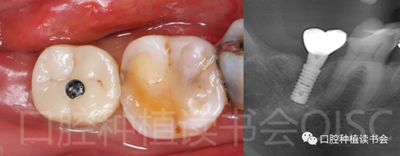

5.4.3 術(shù)后第10周,47戴入最終種植冠,X片確認(rèn)基臺(tái)就位準(zhǔn)確(圖25),以30N.cm扭矩旋緊基臺(tái)螺絲(圖26)。

5.4.4 種植冠封閉螺絲孔后,調(diào)合,拋光,完成最終修復(fù)(圖27);戴牙前CBCT顯示:種植體頰側(cè)骨板厚度為2.88mm;47種植冠獲得了良好的穿齦輪廓,并維持了正常的頰側(cè)牙弓輪廓。